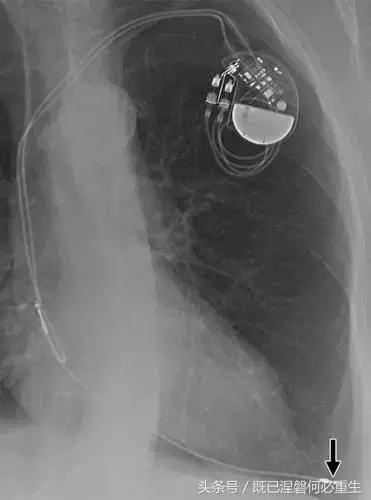

图 1A B 在75岁男性中植入式心律转复除颤器(ICD)的正常部件。

A,额叶胸片显示Medtronic(公司名字)单室ICD。 ICD的基本组件包括发生器,导线和围绕右心室(RV)导线的冲击线圈。 该系统还具有上腔静脉(SVC)中的冲击线圈,其可能不存在于所有系统中。 起搏器没有冲击线圈。 铅固定(见图8A)固定到胸部,并且可能或可能不在胸部X光片上可见。

B,引线通过头连接到发电机(黄色),其保持一个或多个连接端口。 所示系统需要三个端口(一个用于双极起搏或感测元件,一个用于RV休克线圈,一个用于SVC冲击线圈)。 正确放置的引脚将延伸超出连接器(见图9)。 制造商的标志和单个设备标识符的字体被反转,因为发电机被定向以允许在发生器口袋中适当的引线盘绕。 这种定位被设计成减少扭结的风险,这可能导致断裂。 有关制造商徽标的更多信息,请参见图4。